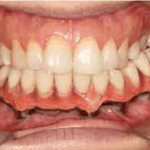

D] CHOICE OF PROSTHESIS

Fixed Prosthesis– might stimulate the bone but can be more difficult to adapt because of anatomical conditions and especially a reduced mouth opening. It also requires a high number of implants, which is not always possible in these patients.

It is recommended in case of short grafts13

FIXED IMPLANT SUPPORTED PROSTHESIS WITH MULTIPLE IMPLANTS

Removable Prosthesis – necessitate fewer implants. The rehabilitation, follow up and oral hygiene are easier. The procedure is cheaper. It can also easily compensate for an aesthetic defect, especially in the anterior part of the mandible14

However, hyposalivation might lead to mucosal irritations and the significant decrease of blood vessels in the oral mucosa renders soft tissues more susceptible to traumas.

The main problem with prosthesis remains the unfavourable implant–crown ratio and axis of the implants, which is not always the same as the axis of the prosthesis, leading to torque forces that may endanger implant survival.

The use of image-guided surgery and surgical guides decreases the risk and minimises the angulation between prosthetic axis and implant axis and also allows precise planning and accuracy of the rehabilitation15,16.

When placement of five implants or more is possible, a fixed ceramic prosthesis can be placed. A fixed hybrid ‘‘Branemark-like’’ prosthesis can be a good alternative for permanent rehabilitation. A bar framework

DENTAL PROSTHETIC REHABILITATION OF A CLASS III DEFECT WITH ORAL IMPLANTS IN THE FIBULA AND SUPRACONSTRUCTION USING A BAR-SUPPORTED DENTURE

can also be proposed for patients wearing a removable denture, as well as O-ring retained dentures or telescopic retention17.